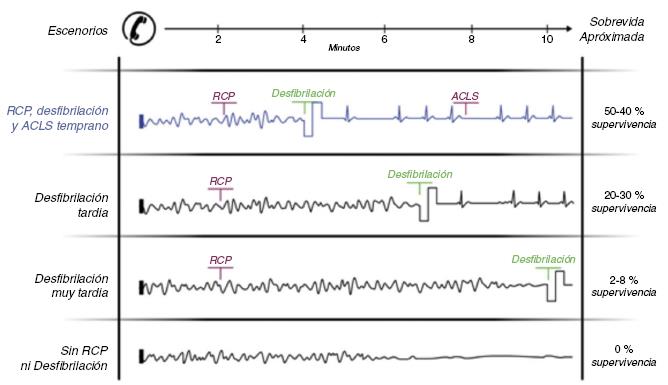

El tratamiento del paro cardiaco súbito secundario a FV o TV es la desfibrilación ventricular31, y cuanto más temprano se realice, mayor será la posibilidad de revertir a ritmo sinusal (Fig. 2). Al primer minuto, el éxito de la desfibrilación ventricular es superior al 90%, y desciende 7-10% por minuto sin reanimación cardiopulmonar (RCP); con RCP la probabilidad de revertir a ritmo sinusal desciende, de un 3-4% por minuto32. La RCP prolonga la ventana de tiempo para poder realizar desfibrilación exitosa33. Se deberá realizar la cadena básica de supervivencia ante un paciente en paro cardiaco. Dicha cadena implica la detección temprana del paciente y activación del sistema de urgencia médica, RCP temprana, desfibrilación temprana, cuidados avanzados tempranos y cuidados tempranos posreanimación. Al realizar todos los eslabones de la cadena de supervivencia dentro de los primeros 5 min del colapso, se mejoran de forma significativa las tasas de supervivencia de estos pacientes31-34 (Fig. 3). La colocación de desfibriladores externos automáticos en sitios públicos junto con la realización de maniobras básicas de RCP por el observador de una víctima de paro cardiaco súbito ha demostrado que mejora significativamente la supervivencia, por lo que se recomienda ampliamente la colocación de desfibriladores externos automáticos y el entrenamiento al público en maniobras básicas de RCP en escuelas, aeropuertos, gimnasios, empresas y lugares estratégicos de la comunidad con alta densidad poblacional35. El desfibrilador automático implantable (DAI) es un equipo con alta posibilidad de revertir a ritmo sinusal un episodio de TV o FV ya que puede desfibrilar en menos de 15 seg una de estas arritmias36-39. La FV produce una contracción irregular y caótica del miocardio ventricular, con la consecuente incapacidad del corazón para mantener el flujo sanguíneo corporal; de no ser revertida a ritmo sinusal, pasará a asistolia y posteriormente causará la muerte del paciente32,36. En la Figura 4 se muestran ejemplos de FV, ritmo agónico y asistolia.

Figura 2 Relación entre el tiempo transcurrido y la posibilidad de revertir a ritmo sinusal con desfibrilación, en casos sin reanimación cardiopulmonar. Adaptada de: Cummins58.

Figura 3 Representación esquemática de varios escenarios de paro cardiaco súbito, RCP, desfibrilación y supervivencia. Observe el escenario en color azul, con aplicación temprana de la cadena básica de supervivencia la posibilidad de supervivencia mejora hasta un 50-60% de las víctimas. RCP: reanimación cardiopulmonar.